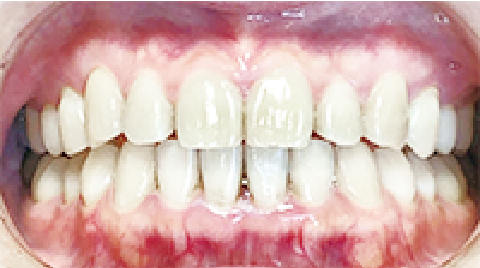

症例 : 8歳 女性

Before

After

主訴

叢生(歯がガタガタ)

乳歯の晩期残存(乳歯が抜けず残ってしまっている状態)

治療方法

床矯正+インビザファースト

総額治療費

660,000円(税込)

治療期間

2年半

治療のリスク・副作用

治療期間が長くなってしまう

改善ポイント

乳歯が抜けないまま放っておくと、永久歯が生えてくるスペースがなく、歯並びが悪くなってしまいます。

下顎前歯が生えてくるのを待ってから顎の拡大を行い、歯並びの調整にインビザファーストを行いました。